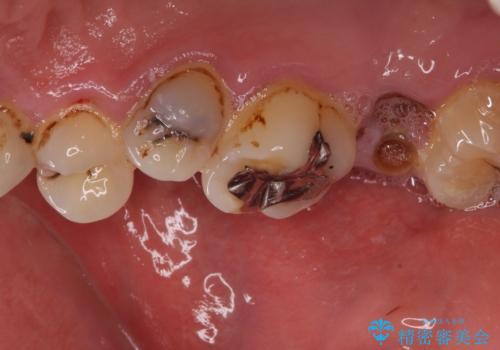

- 前歯や奥歯の虫歯を放置しており、それらの治療を契機に真っ白な歯にしたいとのことで来院された患者様です。

咬み合わせを改善するに当たって、抜歯しなければならない歯や歯列の改善が必要な箇所があったため、矯正治療やインプラント治療から始めていくこととしました。